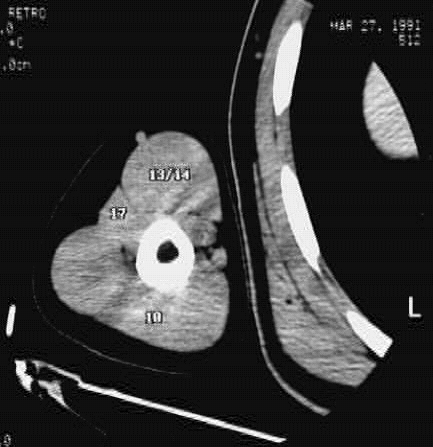

Upper Limbs:Upper Limb Zoom 2 of 2: